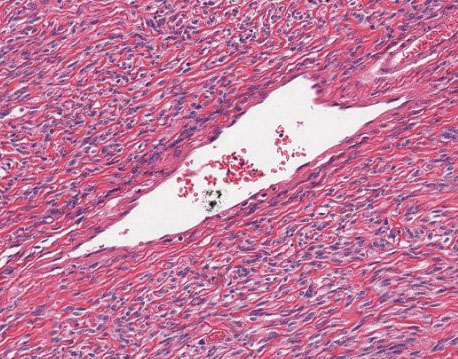

Fibro-obliteratic Duct Lesions

Round / oval fibrous scar that has replaced a bile duct

- seen in chronic obstruction of an extrahepatic bile duct

- onion skinning seen early in the dz, c bile duct surrounded by dense collar of lamellar fibrosis (be careful bc normal large-sized bile ducts can look similar, though the look more atrophic in true onion skinning)

Primary Sclerosing Cholangitis